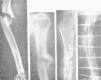

Figura 11. Complicación que se produce por no seleccionar bien el diámetro del clavo; astillamiento del fragmento proximal.

Figura 12. Otra complicación de enclavijamiento cerrado; el fragmento proximal estallado ha sido penetrado por el distal en cuña al impactar; el control radiográfico puso en evidencia el accidente y hubo que retirar el tallo y reducir la penetración; curó sin complicaciones.

Figura 13. Fractura tercio medio fémur con gran desviación fragmentaria, irreducible por interposición muscular, tributaria de la reducción cruenta. La misma, enclavijada y en período de consolidación; callo perióstico exuberante.

La otra objeción es la ya citada por Küntscher y otros autores, de la enorme reacción periostal que se produce en muchos casos, sobre todo en los de fémur, especialmente si ha tenido que ser abierto el foco (por interposición muscular). Esta reacción periostal es explicada por la teoría de los efectos de la presión que el clavo medular ejerce, y por las manipulaciones de reducción, y con gran frecuencia es extensa y bien manifiesta, apreciándose en casi todos nuestros casos un predominio del callo periostal sobre el endostal, lo que permite en muchos casos apreciar en los controles radiográficos la persistencia de la línea de fractura en el endostio, mientras el callo periostal es tan sólido que permite un resultado funcional perfecto; este retardo de formación del callo endostal se corrige lentamente una vez retirado el tallo metálico, lo que permite pensar en la influencia irritativa ¿mecánica?, ¿química?, de la clavija intramedular.

Figura 14. Típico callo exuberante periostal en un enclavijamiento de fémur cerrado.